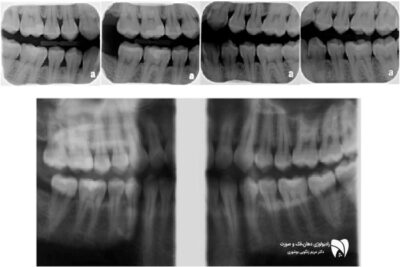

رادیوگرافی بایت‌ وینگ ابزاری کلیدی برای تشخیص پوسیدگی دندان است. در این مقاله با کاربردهای آن آشنا شوید. ضمنا به سوالات مهم در این مورد هم پاسخ دادیم.

رادیوگرافی بایت‌ وینگ: اهمیت و کاربرد آن در دندانپزشکی

رادیوگرافی بایت‌ وینگ موضوعی است که در این مطلب به بررسی آن به عنوان یکی از ابزارهای مهم د...

با رادیوگرافی بایت وینگ به تشخیص بیماری‌ های لثه بپردازید و از 3 مزیت مهم آن برای بررسی دقیق بیماری های لثه‌ها بهره‌مند شوید.

بررسی بیماری‌های لثه توسط رادیوگرافی بایت وینگ

تشخیص بیماری‌ های لثه توسط رادیوگرافی بایت وینگ موضوعی است که در این مطلب قرار است شما با ...